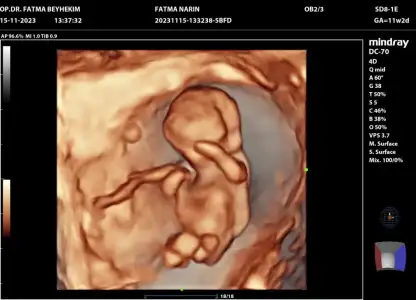

11 hafta simdi sizce nedrYa 6 hafta yazıyor ultrason kağıdında

11 haftlik halii erkek demisdin dha beli deil doktor tahminm var dedi ama erkn 2 hafta sonra kesin soyliycm sna dedi 3 aylik olucaz .. erkn ogrncem cinsyti acaba erkek oldu icin mi erkn . Digr kizlrm 5 ve 6 ayda beliydiBu kesinlikle erkek

Anldmm tskr .. canm doktr da bana iki hafta sonra gel dedi kesin soylicem dedi . 11 haftyz suan acaba bukdr erkn soylemsi erkek olablrmi kizlrin gec belli oluyoValla ben bilmem. Anlamam da. Ama çok erken. 17.haftaya kadar kız dediler sonra erkek oldu bizim. Kim ne derse desin inanmayın.

Evet o zaman erkek görmüş olabilir ama sadece tahmin. Bizim oğluşun pipisi gözükmedi 17 ye kadar. 2 hafta sonra söylemesi de çok güvenli olmaz ama renkli ultrasonu varsa kesin görürAnldmm tskr .. canm doktr da bana iki hafta sonra gel dedi kesin soylicem dedi . 11 haftyz suan acaba bukdr erkn soylemsi erkek olablrmi kizlrin gec belli oluyo